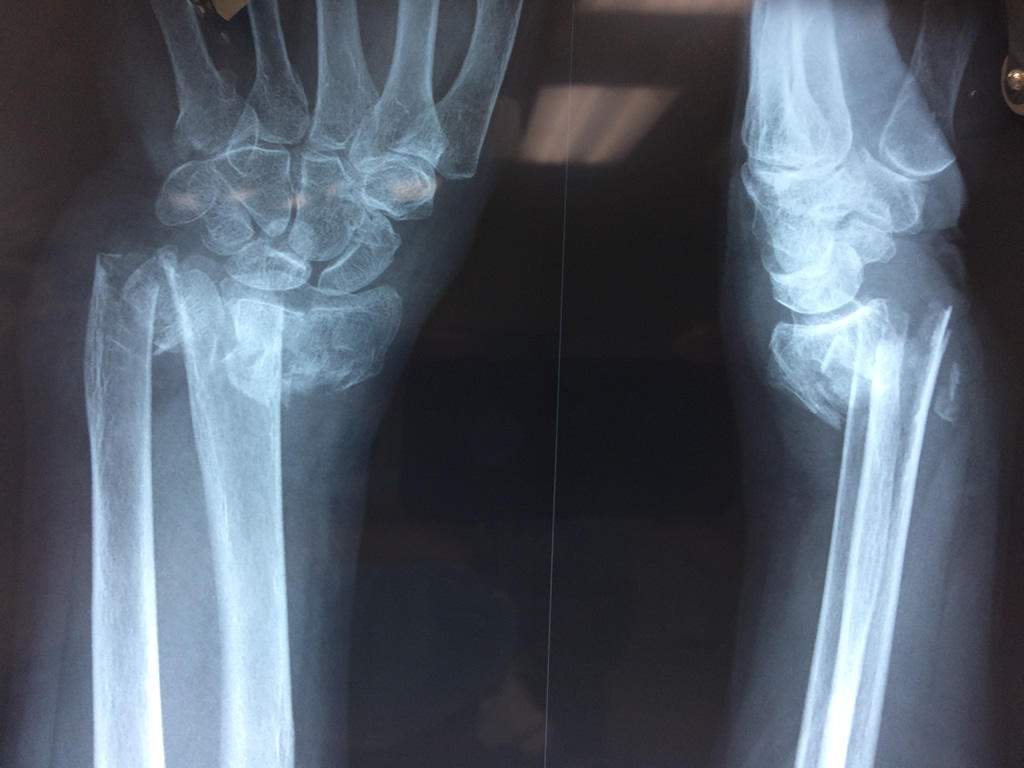

Los procedimientos más comunes en cirugía de la mano son aquellos destinados a reparar traumatismos, incluyendo lesiones de tendones, nervios, vasos sanguíneos, y articulaciones; huesos fracturados; y quemaduras, cortes, y otros daños de la piel.